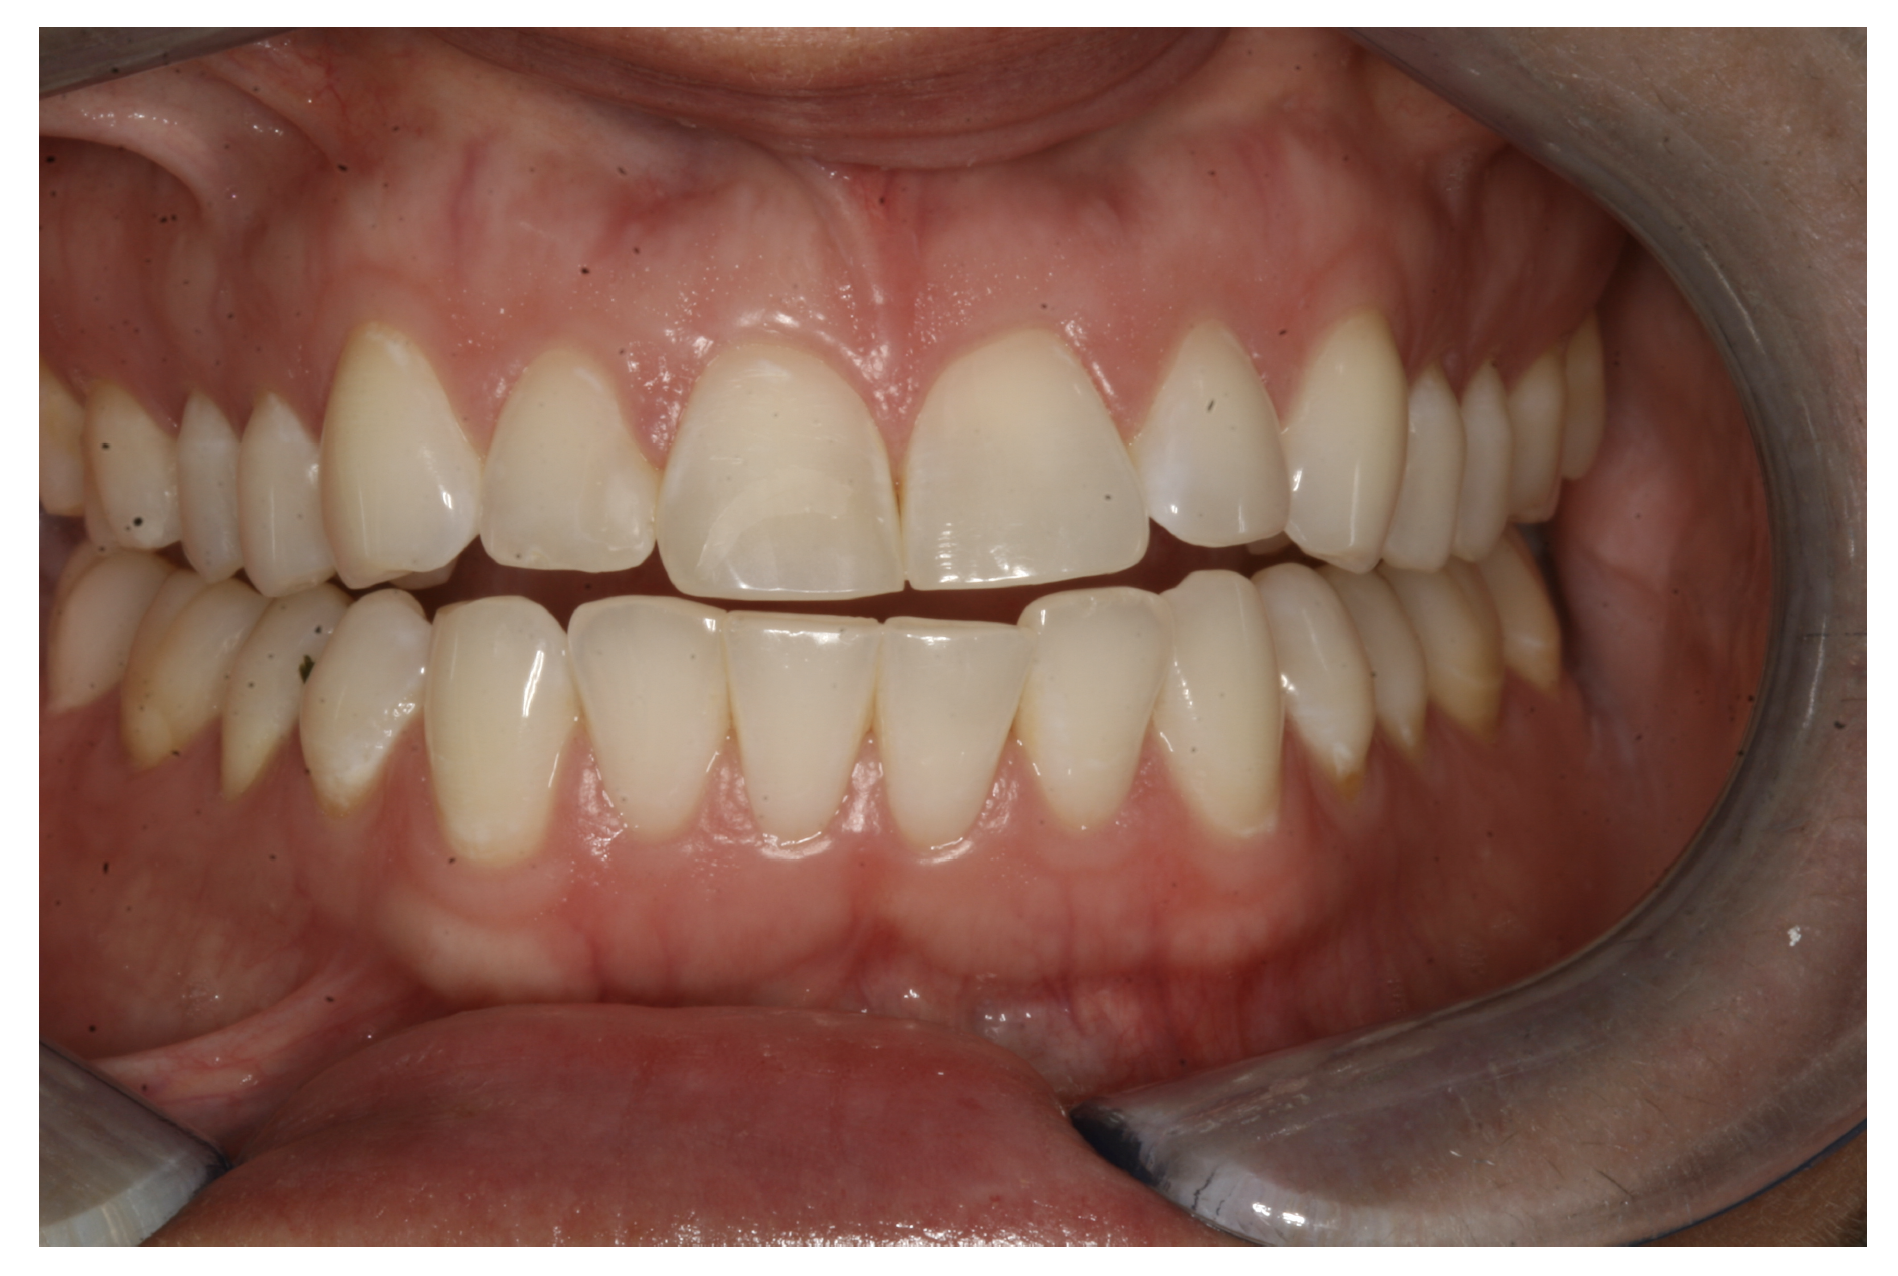

For the case in Figure 9 through Figure 11, the patent presented for an initial consultation with bonding completed on teeth Nos. 7 through 10 a few years prior with a chief complaint of not liking the way the resin bonding looked and how it was wearing. Up to this point, the bonding had repeatedly chipped and been repaired three times already. The patient's canines also exhibited signs of incised wear and flattening, which she did not like. Based on the patient's goals for her smile and her financial budget, she elected to have porcelain veneers completed on teeth Nos. 6 through 11. The total esthetics of the case design were somewhat limited given that the patient's esthetic zone included her posterior teeth and mandibular anterior teeth. Therefore, the color and characteristics of the veneers had to match her existing dentition closely.

In another case, the patient presented with very thick, bulky, over-contoured veneers done on teeth Nos. 7 through 10 when she was a teenager. There also was some recession and staining at the margins (Figure 12). The clinician decided to restore teeth Nos. 6 through 11. A preparation design was required with provisionals removed. As tooth structure could not be regrown, the practitioner made the best of the situation. There was good gum health, which is important for isolation and marginal seal. The clinician cemented with a universal, doing six units at one time. Minimal cleanup was required. At a 1-month follow-up visit, although tissue still was settling in, the contours were natural. After a year (Figure 13), the gum filled in nicely and was in excellent health, and there was good color stability and seamless marginal integrity.